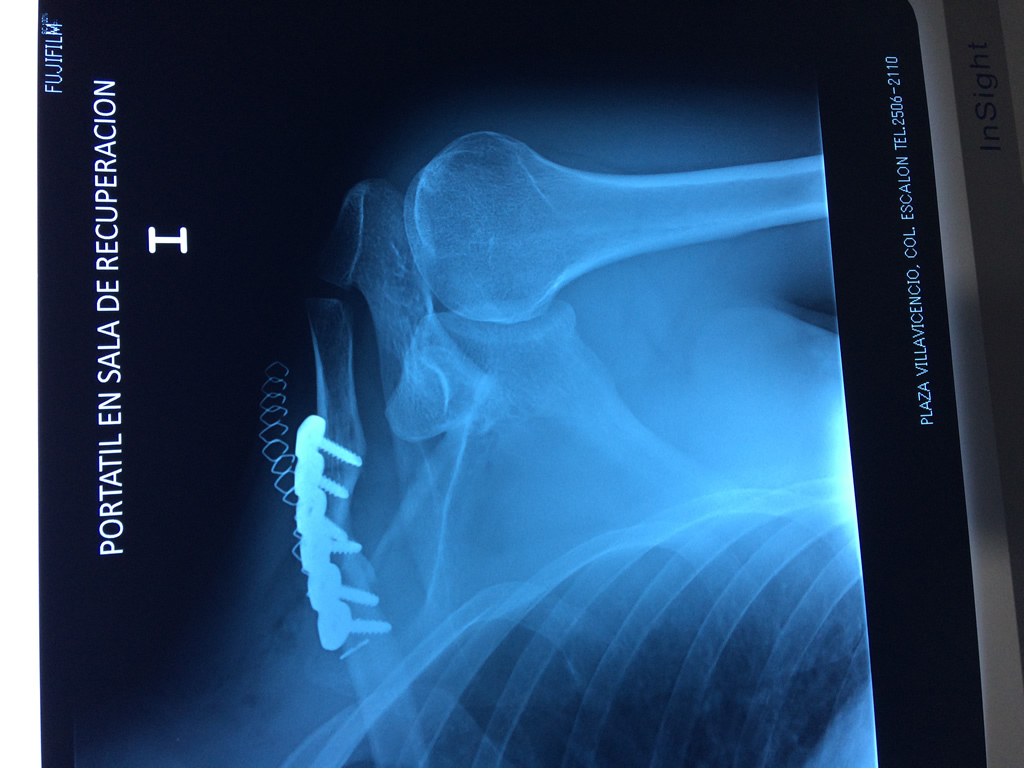

Húmero - Clavícula

La clavícula es un hueso largo, con forma de "S" itálica, situado en la parte anterosuperior del tórax. Junto con la escápula forman la cintura escapular. Se puede palpar por toda su longitud y se extiende del esternón al acromion de la escápula, siguiendo una dirección oblicua lateral y posterior.

Se considera el único medio de unión entre el miembro superior y el tórax. A pesar de su aspecto, similar al de un hueso largo, posee una estructura semejante a la de un hueso plano, ya que carece de epífisis y de diáfisis, lo que la harían entrar dentro de la clasificación de hueso largo. Carece de un canal medular propiamente dicho.